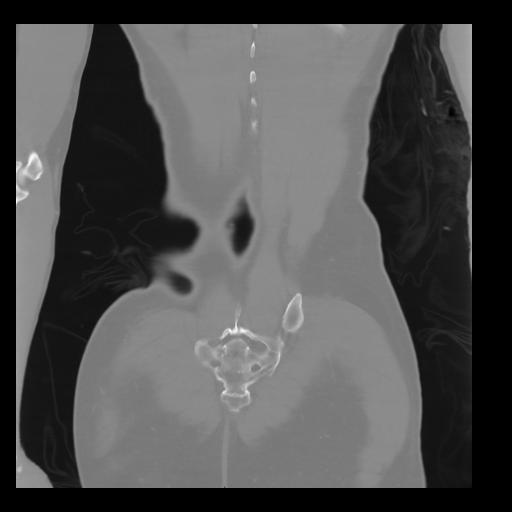

35 CUERPO,CE,Coronal,3.000,CUERPO,Coronal,